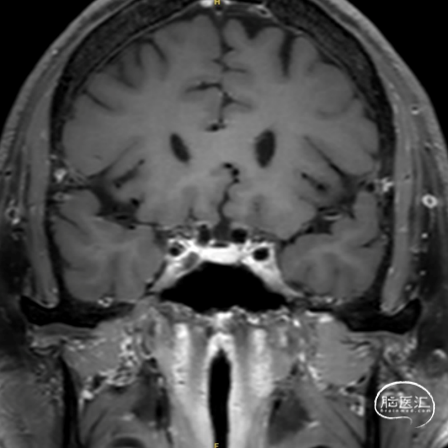

男性,38岁。

主诉:突发头痛、头晕1天。

既往史:无特殊。

查体:GCS 评分14分。

1. 蛛网膜下腔出血

2. 左侧大脑中动脉分叉部动脉瘤